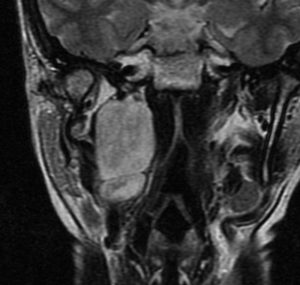

典型的な例2

40代で発症したものです。手術リスクが高いので定位分割放射線治療 fSRT をしました。50グレイを25分割,1回線量2グレイです。以来,18年間が経過しますが腫瘍は2/3くらいに縮小して,そのままです。新たな症状もありません。この腫瘍への手術侵襲は大きいので定位放射線治療は有力な治療選択肢です。